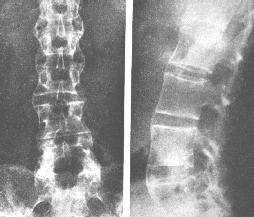

AS ①晚期 ②重度 病史:5年+

- 治疗

治疗后骶髂关节疼痛消失,腰椎前屈、背伸侧弯活动自如,膝关节无压痛感,复查血沉、C反应蛋白、等各项检查均已达到临床康复的标准。